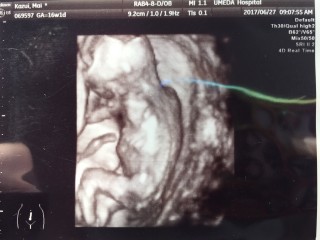

写真:16w1d:ゆっきぃさん:一卵性双子

*BPD3.3cm*FL2.0cm

週数ジャストの大きさだそうです(*˘︶˘*)

上の子が♂♂♀で今回のbabyは、、、なんか付いてそうですね〜!との事でした(*^^*)

長女の遊び相手にもう1人女の子欲しかったけど、男の子3人賑やかになるな〜。・*・:≡( ε:)

でもまだ確定ではないらしい!次回で確定するといいな♬︎♡ ママは貧血で鉄分の注射をされました〜これから毎回健診の度に注射が必要との事、、、